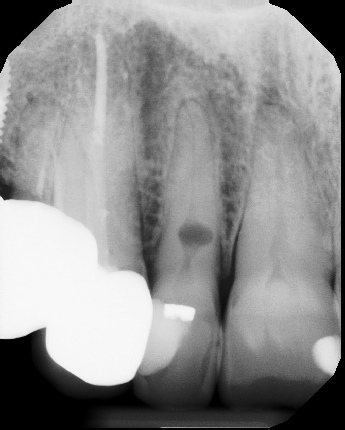

COMPLICATED ANATOMY LARGE LESIONS CALCIFIED CANALS PERFORATION / RESORPTION SEPARATED INSTRUMENTS SURGICAL CASES RETREATMENT / pOST REMOVAL OPEN APICES ACCESS THRU CROWNS Root Canal Case Portfolio

6 mos.